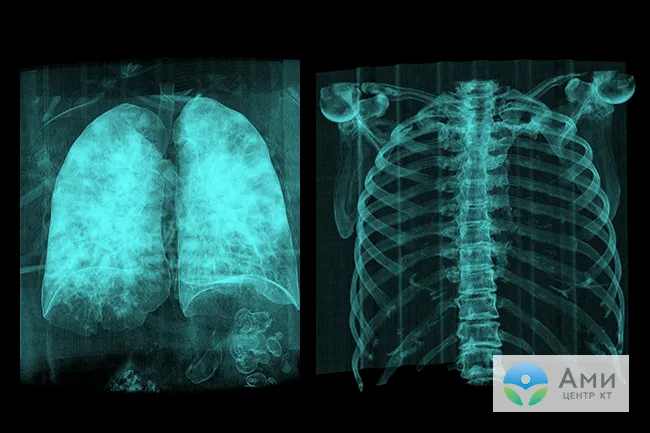

Как коронавирус влияет на легкие и дыхательную функцию

По данным открытой научно-исследовательской базы PubMed, наиболее распространенные осложнения после коронавируса (вирусной пневмонии) со стороны дыхательной системы, которые снижают качество жизни и сокращают функциональный объем главного дыхательного органа — это пневмофиброз и другие интерстициальные заболевания легких (ИЗЛ). Прогноз наименее благоприятный у пациентов, которые перенесли тяжелую пневмонию с обширным воспалением (КТ-3 и КТ-4) и диагностированным на КТ симптомом «булыжной мостовой». Выраженность фиброзных изменений может быть небольшой (при КТ-1 и КТ-2) — в этом случае пациент даже не почувствует, что в легких произошли изменения.

Фиброз — это защитная реакция организма на воспалительный процесс или травму. Она наблюдается приблизительно у 10-15% пациентов, переболевших вирусной пневмонией, ассоциированной с COVID-19. При фиброзе легких наблюдается патологическое разрастание соединительной ткани в альвеолярных капсулах и между ними (в интерстиции — легочном матриксе). В результате эластичная ткань дыхательного органа грубеет, образуются рубцы, сокращается пространство, предназначенное для кислорода.

Диффузный фиброз в разных сегментах приводит к деформации соединительнотканного каркаса легкого (по аналогии с ХОБЛ) и может существенно влиять на дыхание, вызывая непродуктивный кашель, одышку, резистентность к физическим нагрузкам.

Таким образом, у некоторых пациентов, переболевших вирусной пневмонией, вызванной COVID-19 в острой и тяжелой форме, на КТ могут быть выявлены признаки интерстициальных изменений легких, к которым относится и фиброз легких. К радиологическим признакам в данном случае относится усиление легочного рисунка — уплотнение альвеолярных капсул, интерстиция, нарушение структуры легочного матрикса.

Следствием обширного диффузного фиброза является стойкая дыхательная недостаточность, одышка, кашель — то есть утрата отдельных функциональных участков легких. На лечение пневмофиброза могут уйти месяцы (от 3 до 12), а иногда рубцевание легочной ткани носит необратимый характер.